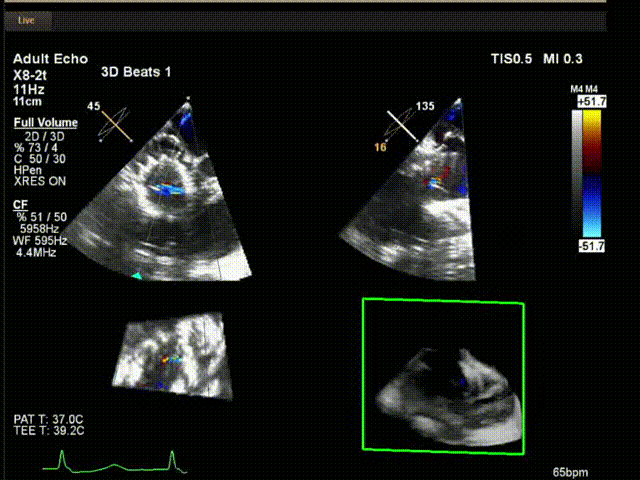

術中超聲

陸方林教授通過遠程線上帶教的方式,與林逸賢教授團隊共同完成了此次LuX-Valve Plus人工瓣膜的首例植入。術后食道超聲提示三尖瓣反流完全消失,無瓣周漏,且LuX-Valve Plus人工瓣膜的兩個夾持鍵成功抓取瓣葉,錨定牢固,人工瓣膜穩定性良好。